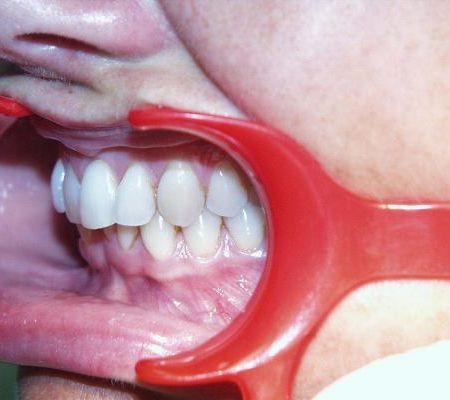

Sehr gute Stabilität nach 12 Jahren

Fallbeispiel 4 zeigt einen häufigen Befund bei erwachsenen Patienten: Die Stellung der Schneidezähne hat sich in beiden Zahnbögen im Laufe der Jahre erkennbar verschlechtert, und die Patienten fühlen sich dadurch zunehmend beeinträchtigt. Die in diesem Beispiel nur geringgradigen Abweichungen im Oberkiefer ließen sich mit nahezu unsichtbaren, herausnehmbaren Alignerschienen behandeln, während die Korrektur der stärkeren Schachtelstellung der unteren Frontzähne eine festsitzende Zahnspange erforderte. Auch hier ist nach der Korrektur die Verwendung innenliegender aufgeklebter Stabilisierungsdrähte über viele Jahre hinweg ratsam.